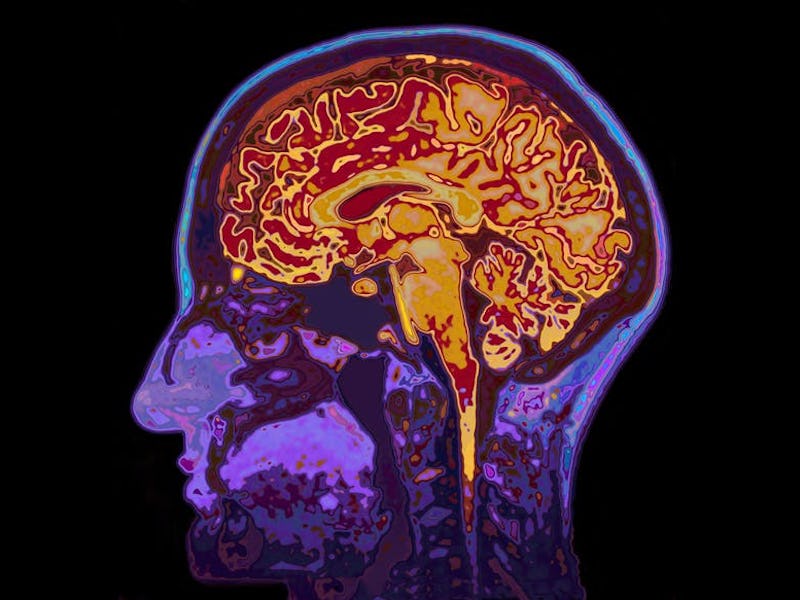

Our brain is the most complex organ in the body. Not only does it control basic life functions like breathing, organ function, and movement, it’s also behind more complex processes – everything from thought, controlling our behavior and emotions, and creating memories. But despite how important our brains are, many people still know very little about it.

Even when we’re sleeping, our brain is always active. It has to be to keep us alive. But different parts of the brain are responsible for different functions. The brain is divided into four pairs of lobes on each side of the head. The frontal lobes are located near the front of the head and the temporal lobes are just beneath them. The parietal lobes are located in the middle and the occipital lobes are at the back of the head.

The frontal lobe is often associated with what “makes us human”. It’s involved in cognitive processes such as reasoning, learning, creativity, attention and controlling muscles used for movement and speech. It also helps us make memories, and learn to regulate emotions and behavior.

The parietal lobes are involved in a mixture of functions. These include sensory and numerical processing, as well as visuospatial information – which is needed for movement, depth perception, and navigation. The temporal lobes also receive information relating to sounds – including the language we hear – as well as in-memory processes. The occipital lobes are involved in visual processing. When light enters your eyes, it’s transmitted by nerves to this region and converted to an image that you “see”.

The lobes are further divided into functional regions. These are individual regions of a certain lobe that’s responsible for specific functions. For example, an area in the frontal lobe called Broca’s area is specifically involved in language production and comprehension.

By scanning the brain, scientists can measure when and which areas become more active in the brain by looking at which areas experience an increase in blood flow, which delivers the extra oxygen the area needs to function or perform a task. Knowing which parts perform which tasks are important both for research, and when performing surgery.